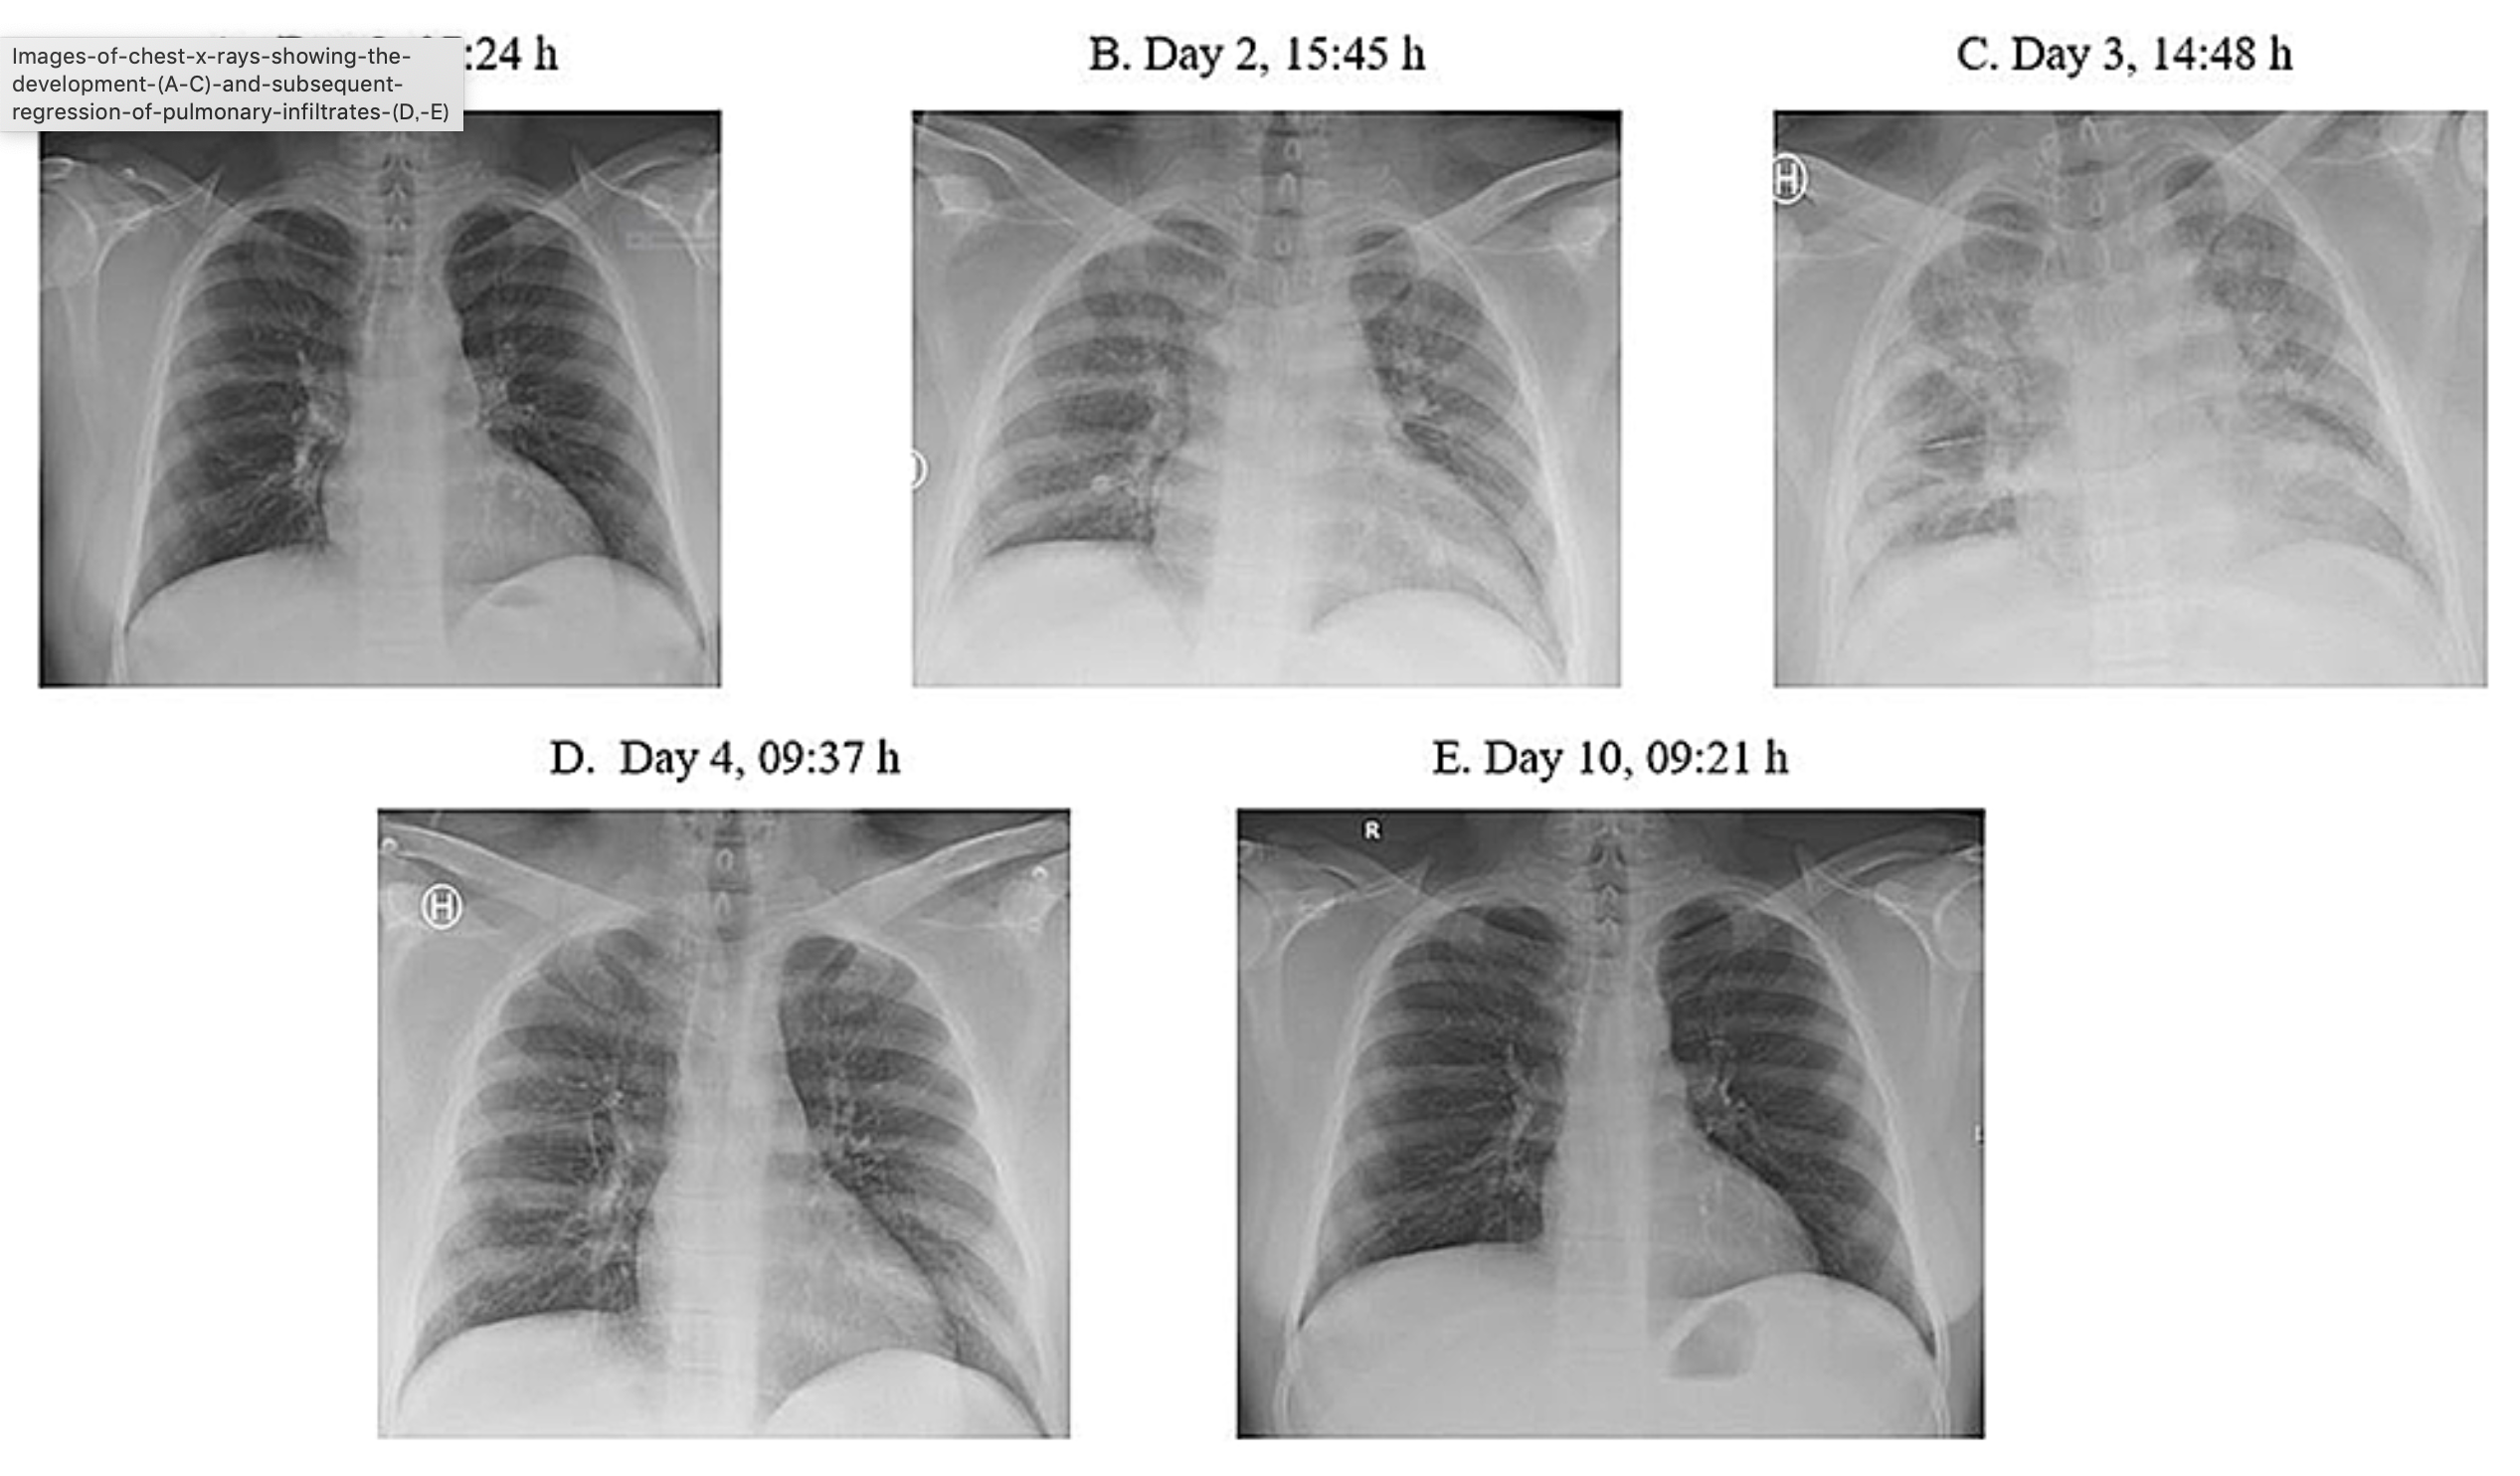

- 心肺停止で搬入された60才代男性の第21病日に施行された上段Tl、下段BMIPPの心筋イメージングである。

- PCPS離脱後の第21病日にTl/BMIPP dual SPECTが施行された。

- Tlは前壁と側壁が中等度に集積低下し、BMIPPでは同部位が高度集積低下―欠損となっている。

- 左室は拡大し、右室が明瞭に描出されている。

- 冠動脈支配領域に一致するミスマッチの集積低下であるため、再度冠動脈造影が施行され、アセチルコリン負荷により、左前下行枝と回旋枝の同時spasmが確認された。

- 高度に心収縮力は低下したままであるが、spasm予防を含めた治療が続いている。

- 心源性ショックの原因としての多枝冠攣縮の診断にTl/BMIPPイメージングが大きく寄与したと言える。